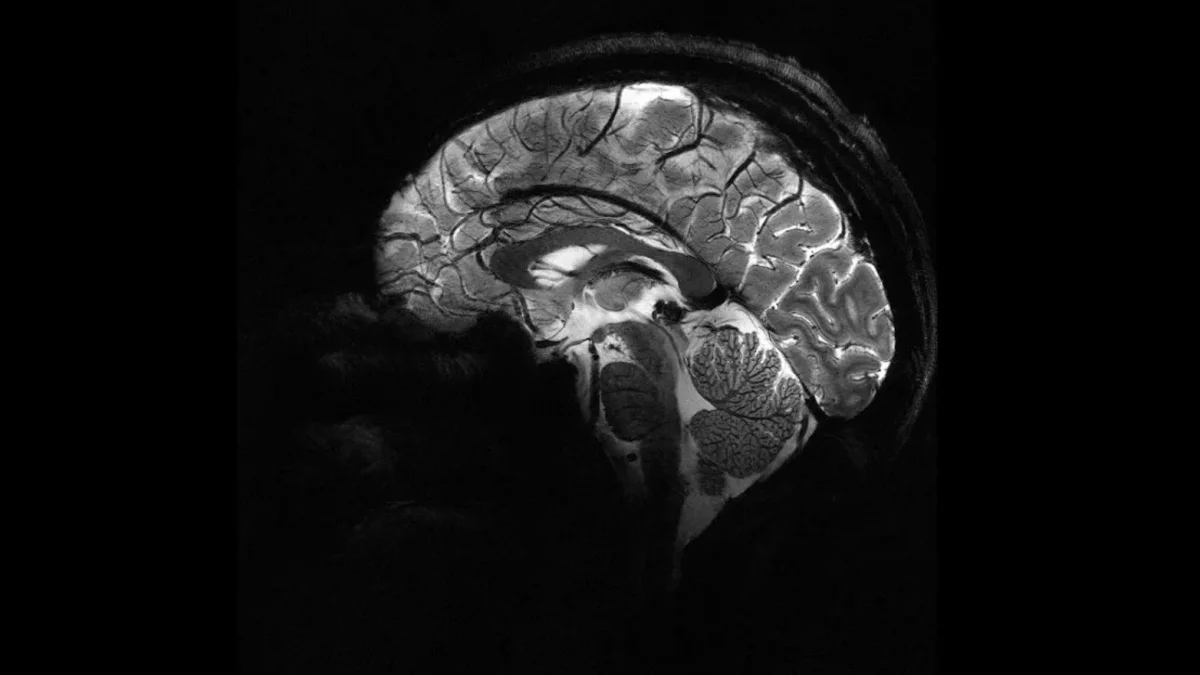

Εκπληκτικές εικόνες έδωσε στη δημοσιότητα το πιο ισχυρό μηχάνημα απεικόνισης μαγνητικού συντονισμού (MRI) στον κόσμο.

Σε μόλις 4 λεπτά, αυτός ο μοναδικός τομογράφος μπορεί να αποδώσει εικόνες σε ανάλυση που θα χρειαζόταν ώρες για τον μέσο σαρωτή σε ένα νοσοκομείο, δίνοντας στους επιστήμονες ένα άνευ προηγουμένου “παράθυρο” στον ανθρώπινο εγκέφαλο.

Αλλά πέρα από την ωμή ταχύτητα της διαδικασίας, η ανάλυση που προσφέρει ο σαρωτής μαγνητικής τομογραφίας Iseult μπορεί να επιτρέψει στους επιστήμονες να μελετήσουν υγιείς και άρρωστους εγκεφάλους σε ζωντανούς ανθρώπους με πολύ πιο υψηλό επίπεδο λεπτομέρειας απ’ ό,τι είχε η επιστήμη στα χέρια της μέχρι σήμερα.